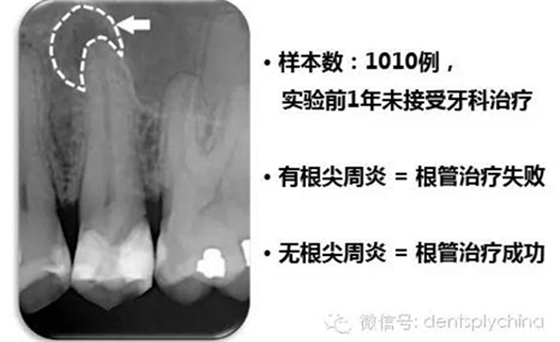

成功標準: 根尖周健康 = 沒有根尖周炎

根管治療成功率和嚴密的冠部封閉密切相關(guān)

作者的結(jié)論

"對于控制根尖周感染而言,冠部修復(fù)的質(zhì)量比根管治療的質(zhì)量更重要。"

蘇黎世大學(xué)根管治療病例顯微CT研究